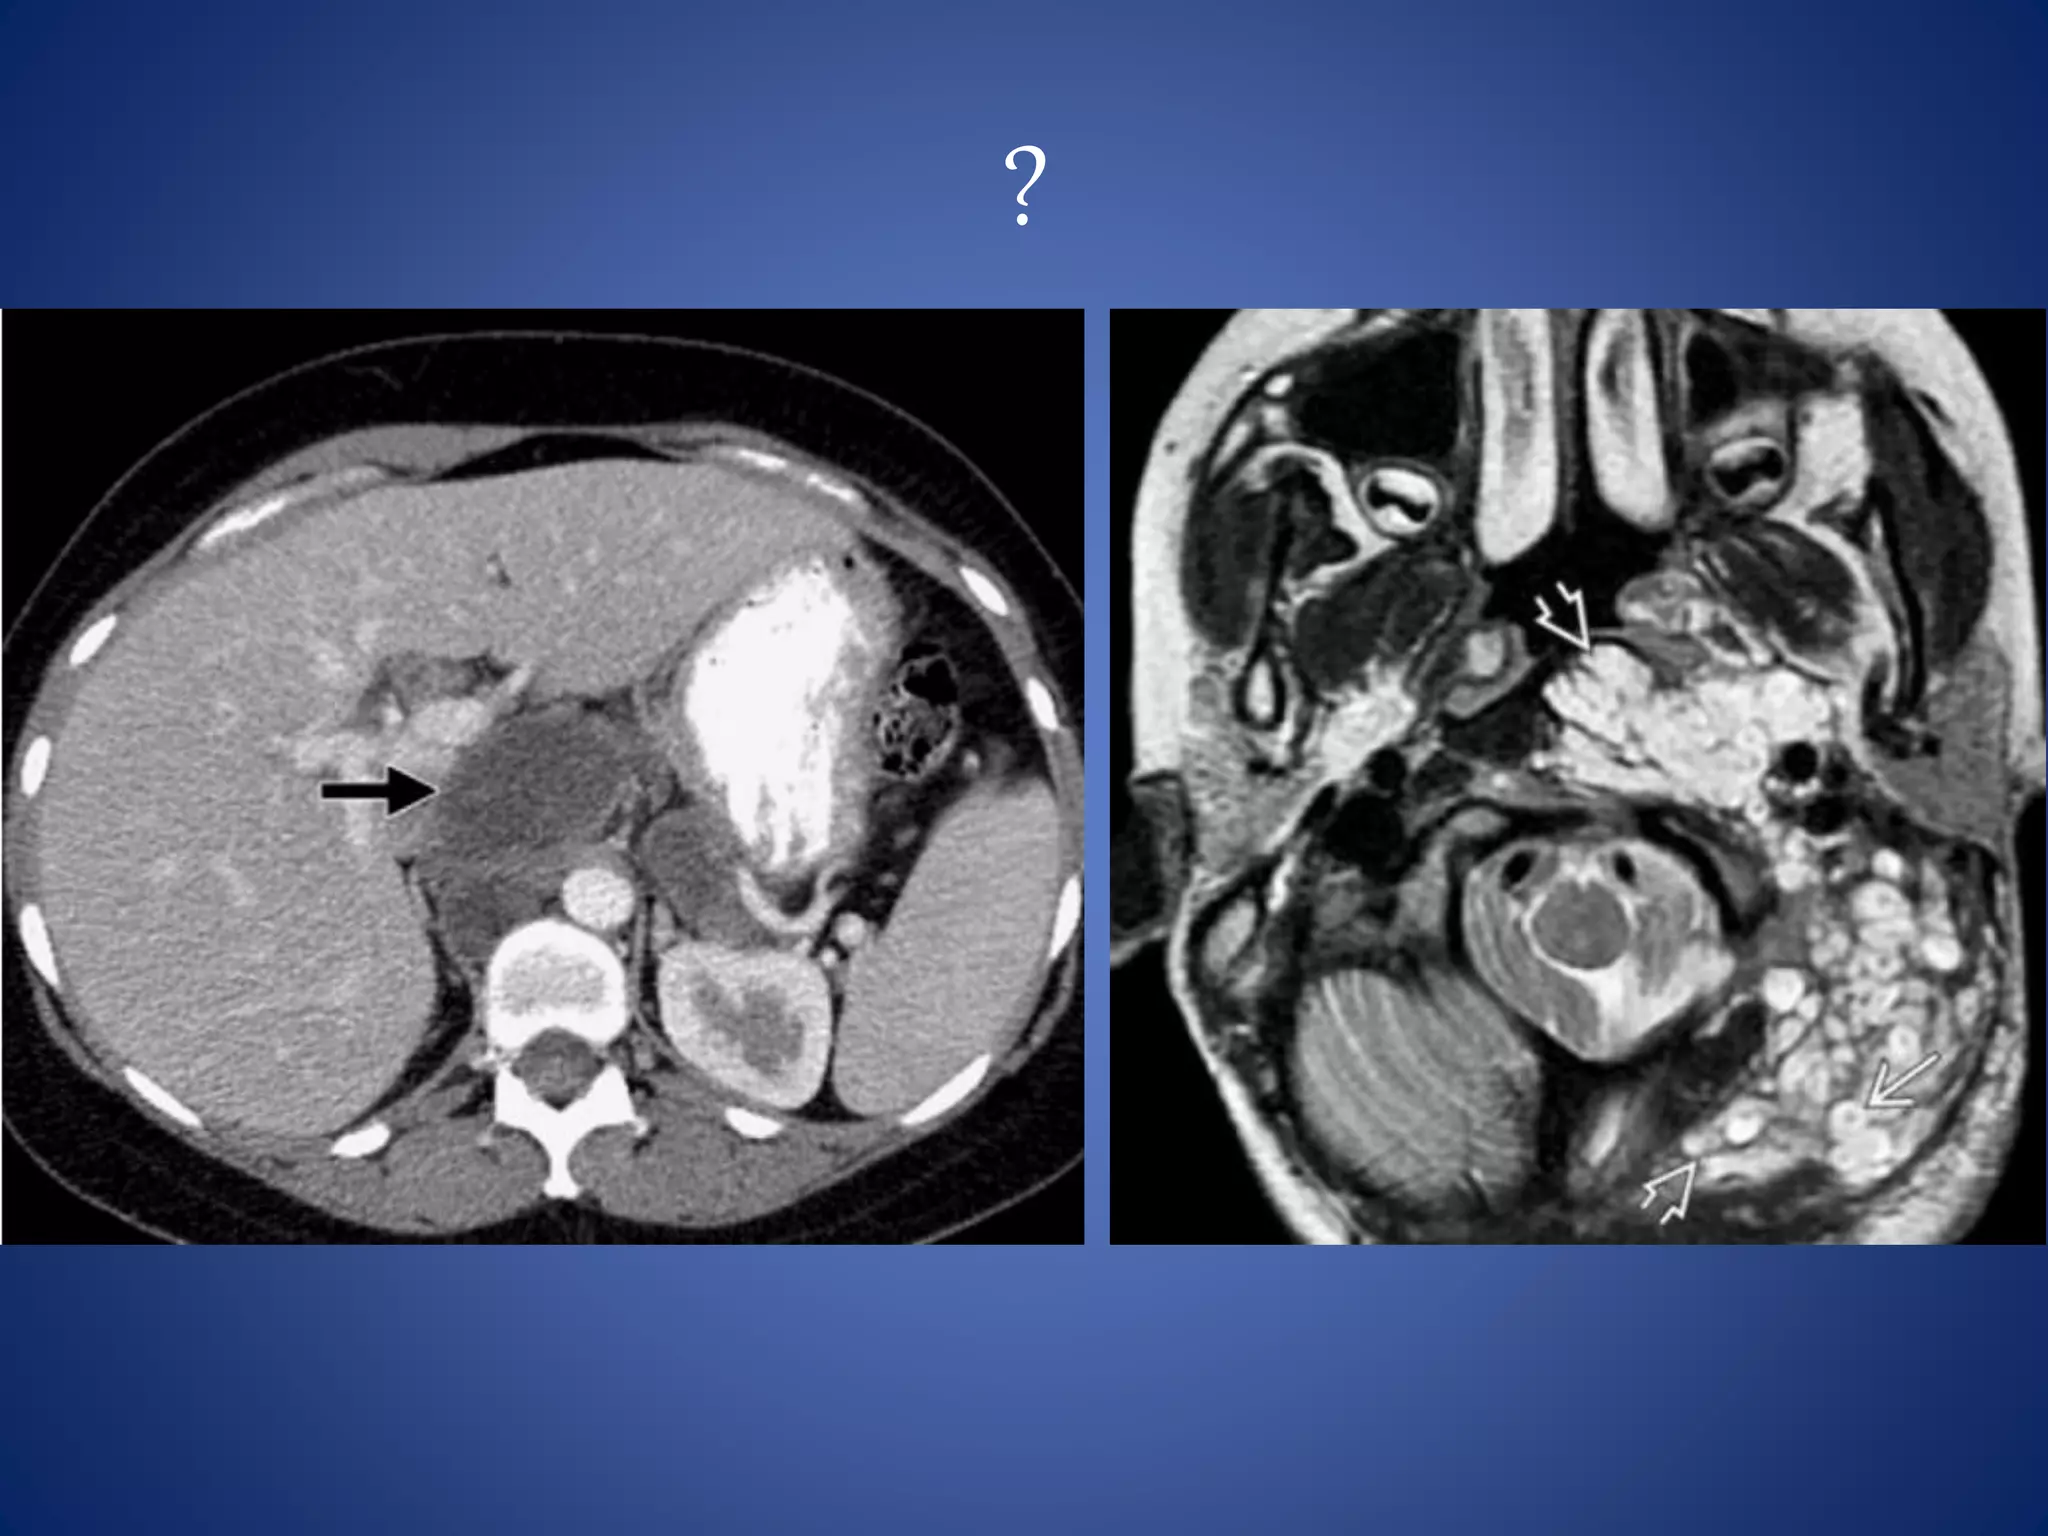

• #74 Leiomyosarcoma --- The presence of extensive necrosis in a retroperitoneal mass, with contiguous involvement of a vessel, is highly suggestive of leiomyosarcoma 6% of leiomyosarcomas arise from the IVC

• #76 Neurofibroma --- well defined round homogeneously hypoattenuating lesion (20–25 HU) because of the presence of lipid-rich Schwann cells and adipocytes and entrapment of adjacent fat. Patient with type 1 neurofibromatosis. Brain image : Plexiform neurofibromas (PNFs) -- Multilobulated hyperintense masses with central hypointense "dots" are typical